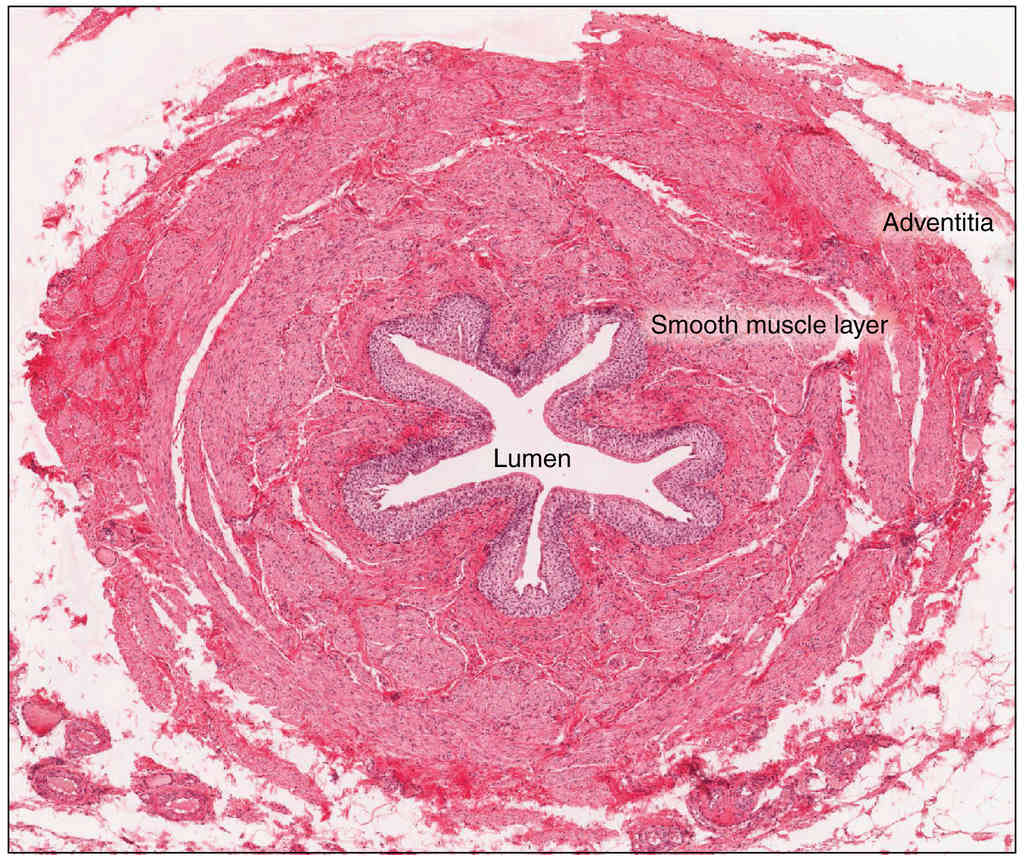

Anatomy, Physiology and Histology

This page is under construction. For now, it is just a resource of the images found in the OpenStax Anatomy and Physiology Handbook. It wil slowly change into a revision tool. Each slide has a number. Use this to refer to the slide. When completed, it will have an unlabelled section, with labelled slides in parallel. On the unlabelled slides, write your answer and use the labelled slide to assess yourself. Keep track by also noting the number on each slide. Improvement at each attempt is important, more so than full marks on a first attempt.